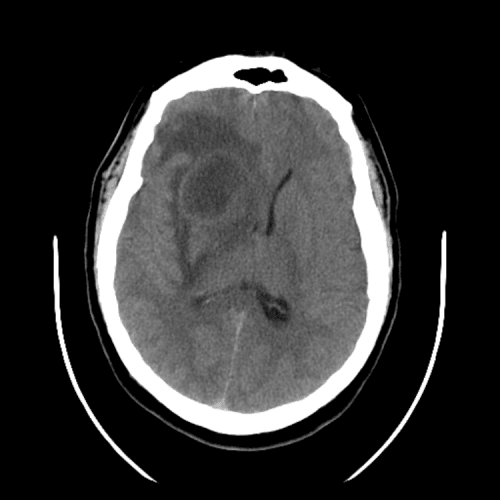

cerebral edema

ACA and MCA territory infarct